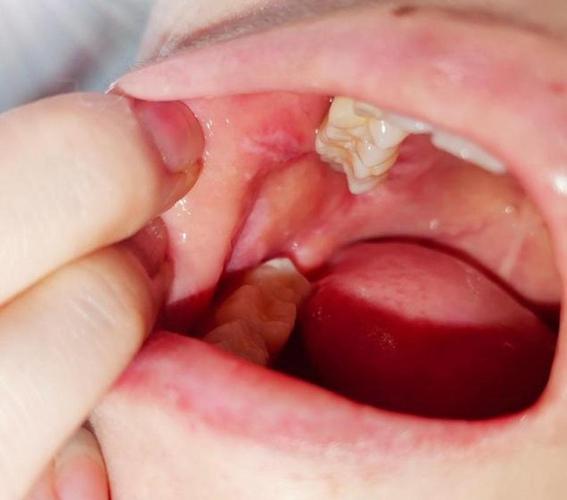

牙龈:

- 危险性: 非常高,牙龈是扁平苔癣的好发部位之一,也是癌变风险较高的区域。

- 特点: 常表现为网状、条纹状,但也容易形成糜烂,疼痛明显,尤其在刷牙时,长期的慢性刺激(如牙结石、不良修复体)会进一步增加风险。

(图片来源网络,侵删)- 危险性: 较高,位于口腔顶部,软的部分。

- 特点: 此处黏膜也较薄,发生糜烂型扁平苔藓时,疼痛和不适感明显,癌变风险也需警惕。